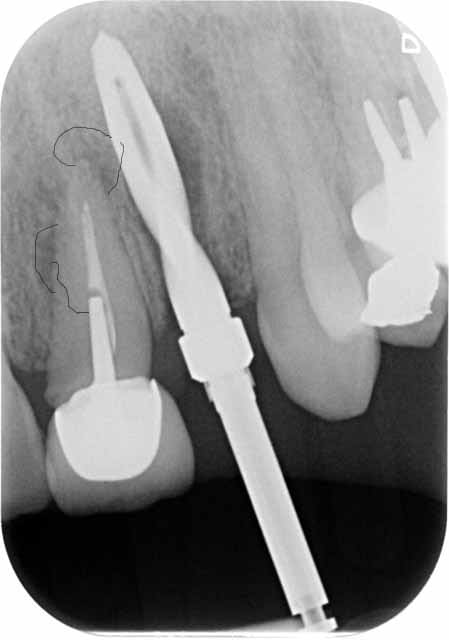

extraction, curetage lésion, implant 3.9 X 16, comblement des lacunes substitut osseux, vis de couverture.

02855 x 00000174 3 hdmbwk - Eugenol

02855 x 0000023a 3 sckpmy - Eugenol

02855 x 0000023b 3 kujdpz - Eugenol